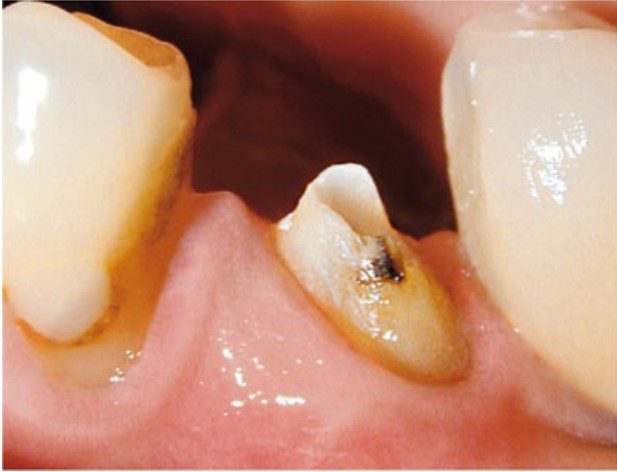

Thông thường, răng cần điều trị nội nha thường đã được phục hồi lớn trước đó hoặc bị bể vỡ và nhiễm khuẩn.

Cần loại bỏ mô sâu răng để ngăn ngừa rò rỉ và giảm nguy cơ mảnh ngà sâu chứa vi khuẩn đi vào ống tủy trong quá trình điều trị.

Lý tưởng nhất là nên có tối thiểu 2 mm mô răng lành nằm trên nướu bao quanh toàn bộ chu vi răng để thuận lợi cho phục hồi sau đó.

Nếu có bất kỳ nghi ngờ nào về khả năng phục hồi răng (xem chương 8) thì cần tháo bỏ hoàn toàn phục hồi hiện có để xác định rõ mức độ và vị trí mô răng lành còn lại.

Việc loại bỏ hoàn toàn phục hồi hiện tại được khuyến cáo trong nhiều trường hợp, vì có thể làm lộ ra các đường nứt ẩn không được phát hiện qua khám lâm sàng bên ngoài hay thăm dò nha chu.